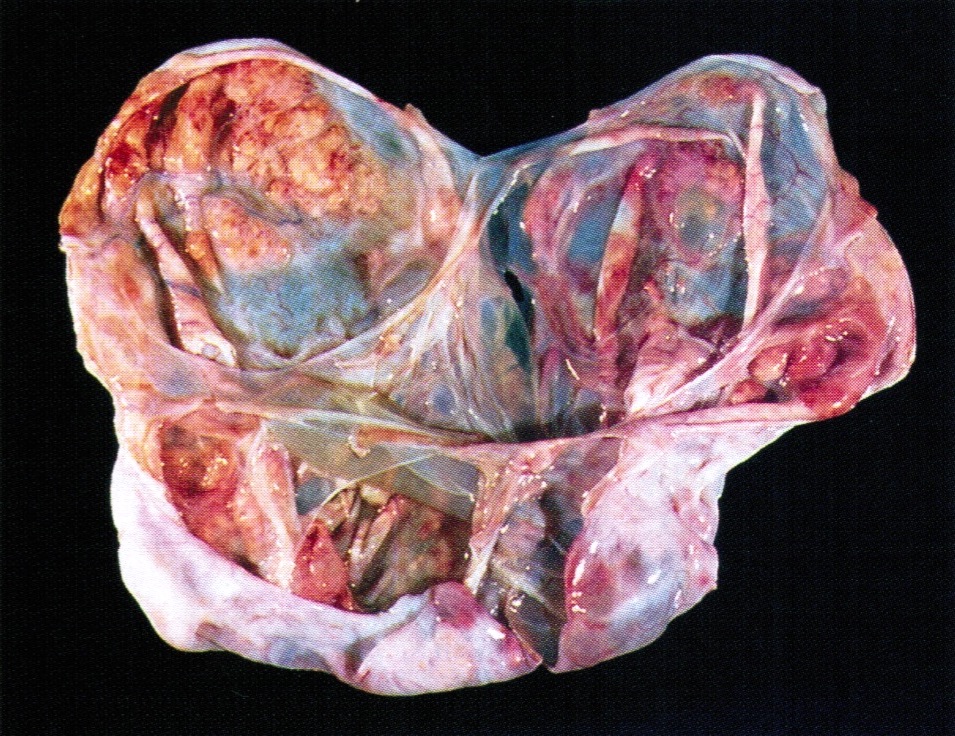

Gross description

- > 95% unilateral and confined to the ovary

- Variable size, average 10 - 12 cm

- Encapsulated with smooth lobulated surface, tan or yellow (depending on the degree of luteinization and lipid content), soft to firm (depending on the amount of fibromatous component), usually solid and cystic with straw colored or mucoid fluid, can have areas of necrosis and hemorrhage

- The more luteinized tumors are more yellow / orange

- May resemble serous cystadenoma

- Rare androgenic tumors tend to be large with thin walled cysts (Arch Pathol Lab Med 1984;108:786)